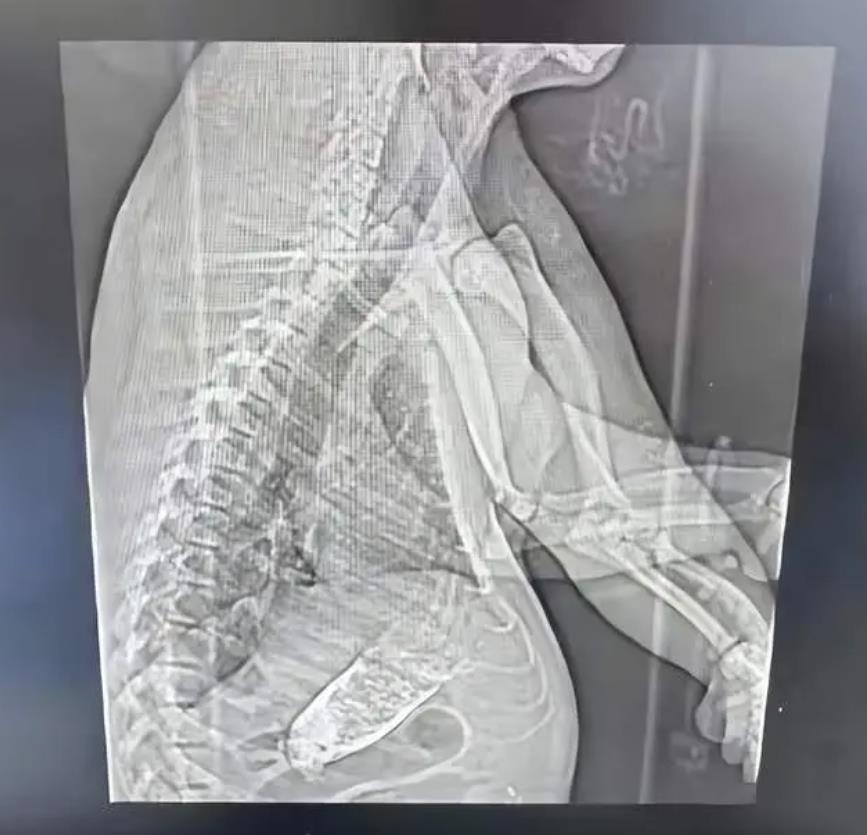

網傳熊貓拍CT圖片。(網絡圖片)

昨晚(2月28日),一則上海三甲醫院CT信息單引發熱議,在病人姓名一欄寫着「熊貓」。發帖網友稱,被檢查的是上海野生動物園熊貓。據內地媒體報道,經過和上海野生動物園核實了解到,居住在上海野生動物園裏的大熊貓「七七」近日因腸梗阻緊急送往上海仁濟醫院南院檢查,目前正全力救治。